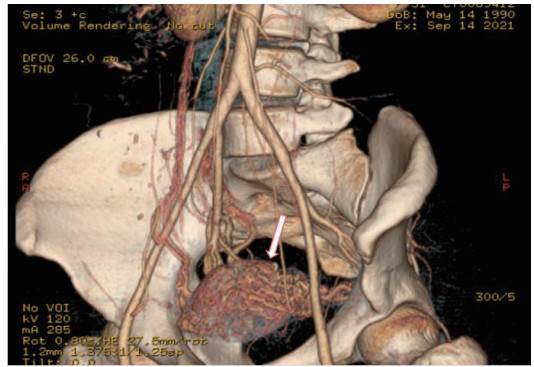

所有患者治疗前行TVDU诊断(图 1),25名诊断UAVF,最终经DSA确诊34名,超声诊断UAVF敏感率为74%,特异率为100%。

| 图 1 经阴道的多普勒超声下UAVF特征性表现 |

TVDU为疾病初筛的手段,敏感度可达74%,特异度100%,可以早期诊断UAVF [11-12]。超声下UAVF特征性表现为无回声区内有丰富红蓝镶嵌血流信号充填,呈“马赛克”或“湖泊样”改变,典型者见静脉血流动脉化表现[12-13]。见图 1。